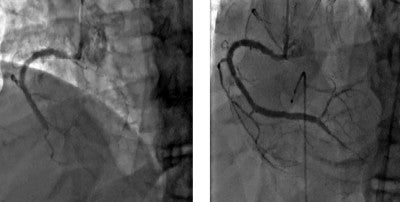

Picture this: An individual comes into a doctor’s or clinician’s office with symptoms of chest pain, shortness of breath and fatigue. The doctor or clinician orders a cardiac catheterization procedure, which reveals that one artery has a 100 percent blockage.